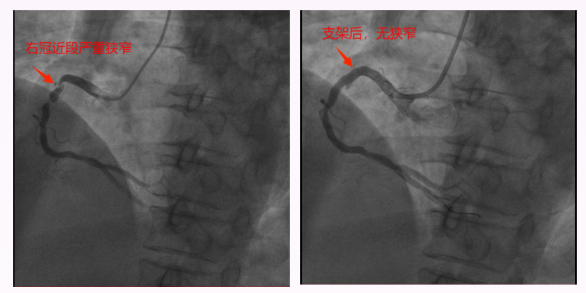

锦旗赠送人:王阿姨及家人。 受表扬者:心血管内科二区刘富湘及全体医护人员。 近日,我院心血管内科二区收到一份特殊的感谢——刚顺利康复出院的王阿姨,将一面印着“医术精湛 务实笃行 真诚敬业 仁心仁德”的锦旗送到医护人员手中,以此表达对医护团队诊疗与照护的认可。 今年60岁的王阿姨有高血压、糖尿病病史,此前因心悸胸闷不适7天入院,症状呈阵发性发作,还伴有压榨感。心电图提示ST改变,结合其基础疾病与症状特点,心血管内科二区主任刘富湘及主管医师罗向卫判断,王阿姨可能患有不稳定型心绞痛,存在进展为心肌梗死的风险。 为进一步明确病情,医护团队迅速为其安排冠脉造影术,结果显示:王阿姨右冠狭窄85%-95%,远端侧枝供血前降支远端;前降支近段硬化伴狭窄90%;回旋支远端狭窄30%。考虑到王阿姨患有糖尿病,若一次手术处理两条血管,不仅手术时间长、单次造影剂用量大,还可能损伤肾功能,且手术风险会显著增高。经过仔细考量,团队最终制定分次手术方案,优先处理狭窄最严重的右冠,并植入一枚支架。 ▲右冠近段支架前后 ▲前降支近段支架前后 一个月后,王阿姨恢复良好,团队再次为其完成前降支手术。术后,王阿姨两支冠脉恢复充足血流,未出现心肌梗死、心衰等不良后果,肾功能也无明显损害,心悸胸闷症状明显缓解,顺利康复出院。 从入院时的焦虑不适,到出院时的轻松安心,王阿姨的好转离不开心内二区医护人员的专业诊疗与悉心照护。这面锦旗,是患者对团队技术与服务的肯定,更是团队继续守护百姓心脏健康的动力。